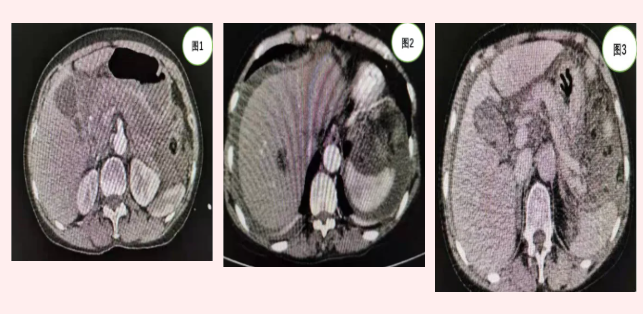

患者張某入院時,急診行全腹CT(見圖1)等相關檢查發(fā)現(xiàn)上腹部包塊但未見明顯肝脾破裂及腹腔積液。由于患者外傷,病情隨時可能加重,主管醫(yī)師張浩杰嚴密觀察病情時,患者腹痛加重,血紅蛋白進行性下降,立即復查上腹部增強CT(見圖2、3)發(fā)現(xiàn)腹腔大量積液。